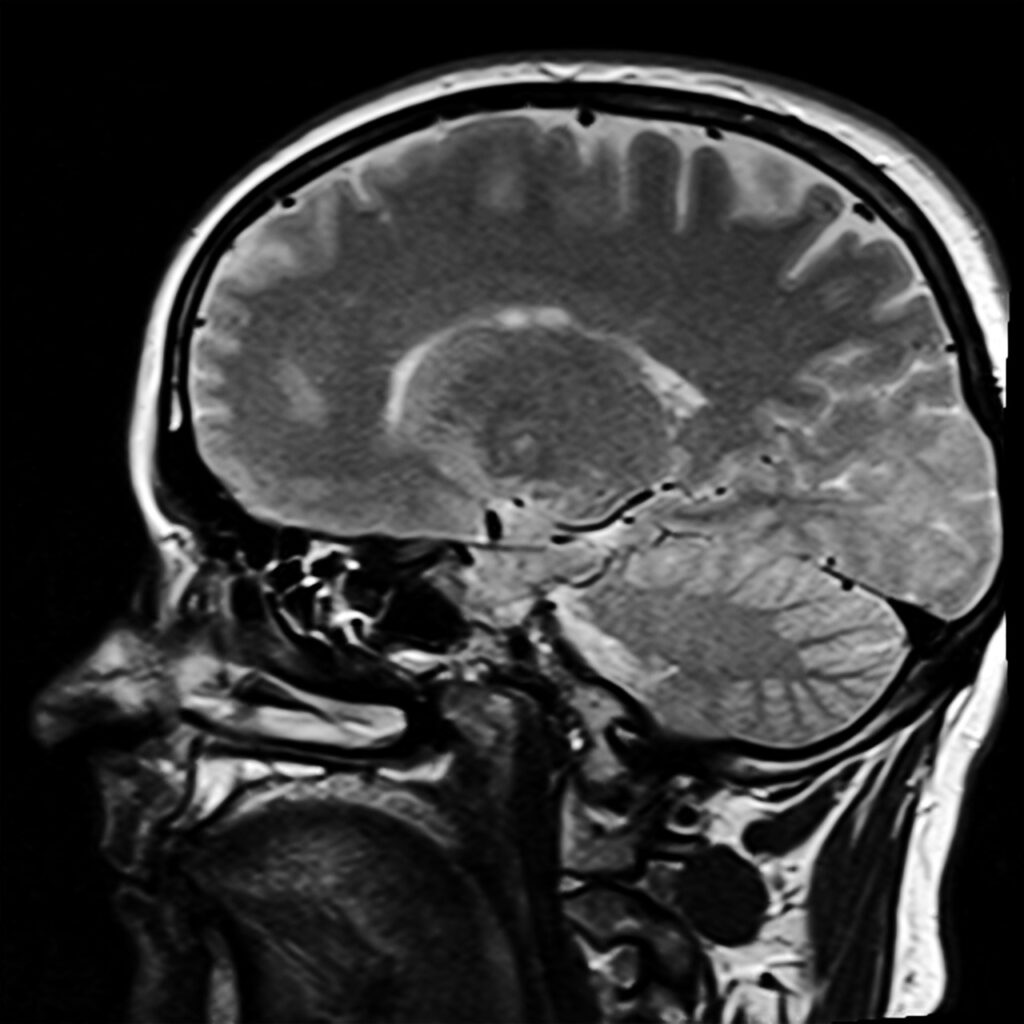

Stefan Kurt, ein Schweizer Film- und Theaterschauspieler, wird langsam in die MRT-Röhre geschoben. Dort drinnen soll er in den nächsten Minuten verschiedene Szenen aus der Dreigroschenoper spielen. Natürlich, aus Platzgründen, nur in seinem Kopf. Dennoch erhoffen sich Jochen Kiefer, Professor an der Hochschule Zürich und der Neuropsychologe Hennric Jokeit, davon eine Antwort auf die Frage: Fühlen Schauspielende wirklich, was Sie da präsentieren, oder ist Schauspiel doch nur „So tun als ob“? Wie fließend diese Grenzen sein können und dass Schauspiel sehr viel mehr sein kann als bloßes Spiel, zeigt sich bei dem sogenannten Method Acting.

Ein paar Szenen aus der Dreigroschenoper später, darf Stefan Kurt die dunkle Röhre des MRTs wieder hinter sich lassen. Auch bei ihm zeigt sich, was die Forscher zuvor schon bei anderen Studienteilnehmer*innen feststellen konnten. Während des Spiels, waren Gehirnareale aktiv, die ein Indikator für Affekte sind. Die Studie bestätigt also, dass Schauspielende die Emotionen, welche sie darstellen, wirklich fühlen.5